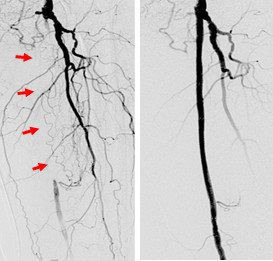

Hình ảnh phim chụp tắc các động mạch chi của bệnh nhân

BSCKII Nguyễn Thế Huy, Khoa Nội tim mạch người lớn, Trung tâm Tim mạch, Bệnh viện E T.Ư cho biết, may mắn ông T. phát hiện bệnh kịp thời, được tiến hành can thiệp nong mạch và đặt stent động mạch nên ngay sau đó ông đã hết đau và tê bì, đi lại bình thường.